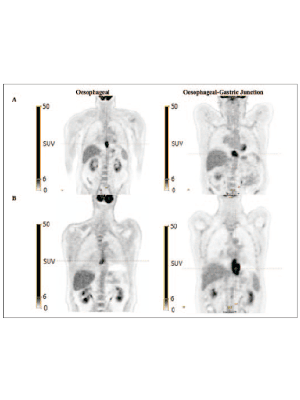

Can AI predict survival from pre-treatment PET images for patients with oesophageal cancer?

Oesophageal cancer is one of the leading causes of cancer death in the UK, with a 10-year survival rate of just 12%. Despite advances in diagnosis and curative treatment, the number of deaths from oesophageal cancer remains high, with over 50% of patients diagnosed with stage IV (incurable) disease. It is potentially curable with surgery but carries a significant risk of complication; the decision to treat is important for patients and clinicians. 18F-fluorodeoxyglucose PET (18F-FDG PETCT) is used as part of staging and is used where CT does not show metastatic disease in the liver or lungs.